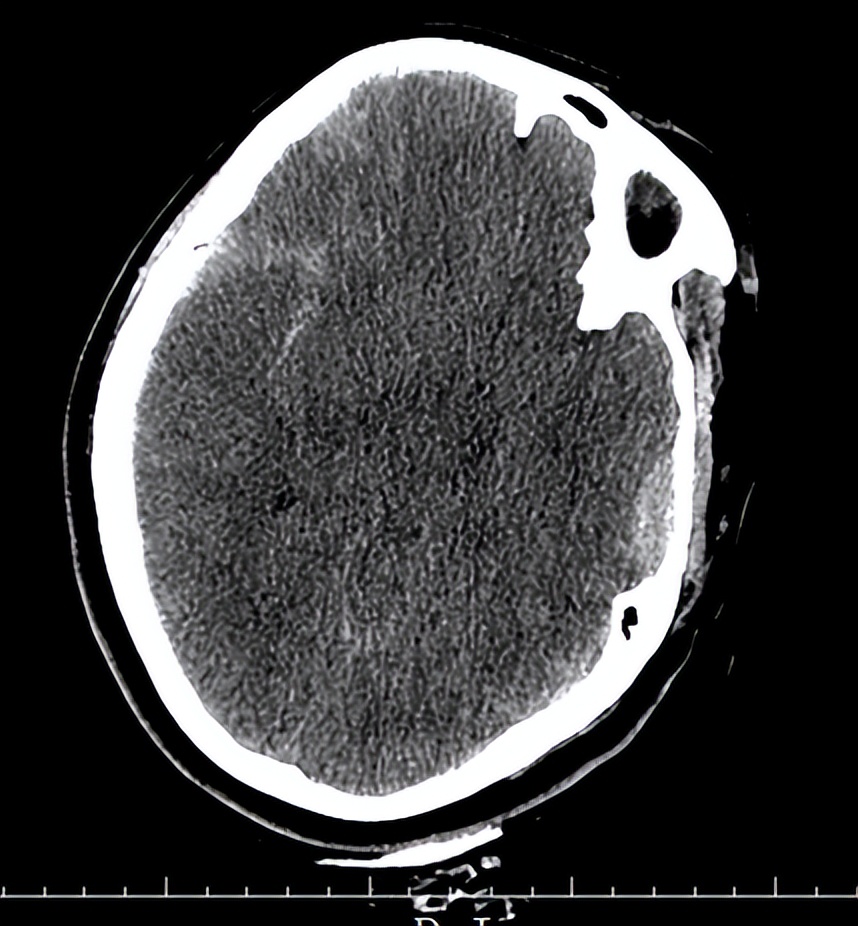

06-07日入院时头CT